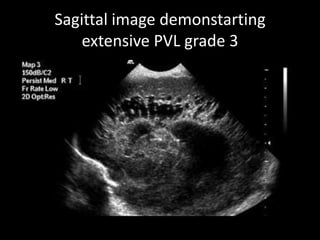

Sagittal image demonstarting

extensive PVL grade 3

• Grade III PVL: Extensive periventricular cystic lesion involving occipital

and fronto-parietal white matter.